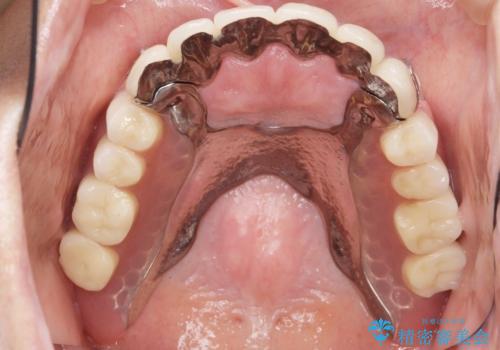

なるべく予算を抑えたいとのご希望から、上顎は入れ歯、右下臼歯部はインプラントによる治療を行いました。

上の前歯は動揺を抑え、入れ歯の着脱にも耐えうるように被せ物を連結させることにしました。

しっかりと咬むことができるようになり喜んで頂けました。

全体的な歯の動揺もなくなり安心して頂けました。

4年経過しましたが問題なく調子が良いとおっしゃって下さいました。

被せ物の種類:メタルボンドクラウン エコノミー

インプラントの種類:スプラインツイスト